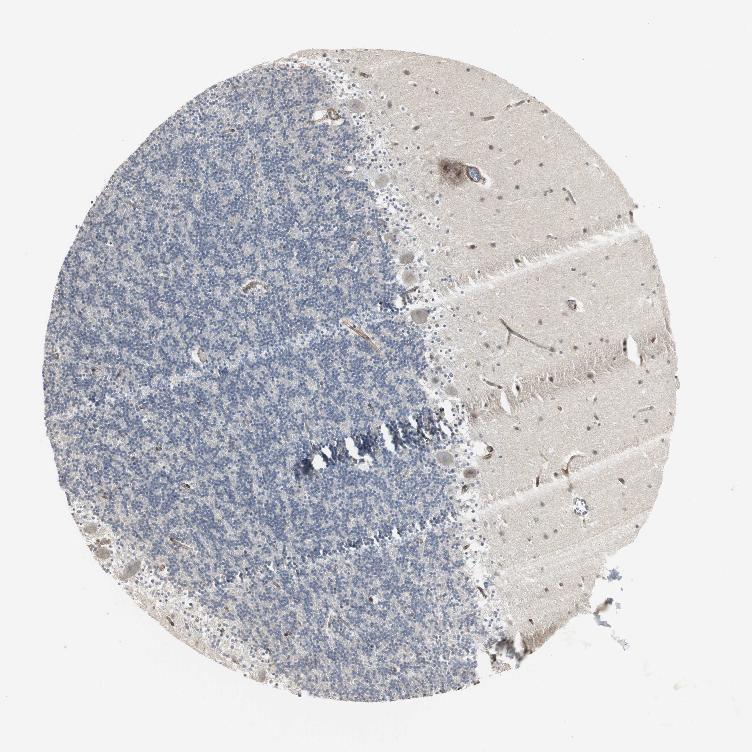

BRAIN CEREBELLUM Show tissue menu

CEREBELLUM - Antibody stainingi

Antibody staining in the annotated cell types in the current human tissue is reported as not detected, low, medium, or high, based on conventional immunohistochemistry profiling in selected tissues. This score is based on the combination of the staining intensity and fraction of stained cells.

Each image is clickable and will lead to virtual microscopy that enables deeper exploration of all samples and also displays staining intensity scores, fraction scores and subcellular localization as well as patient and tissue information for each sample.

Antibody HPA005624

Purkinje cells Low

Cells in granular layer Not detected

Cells in molecular layer Not detected